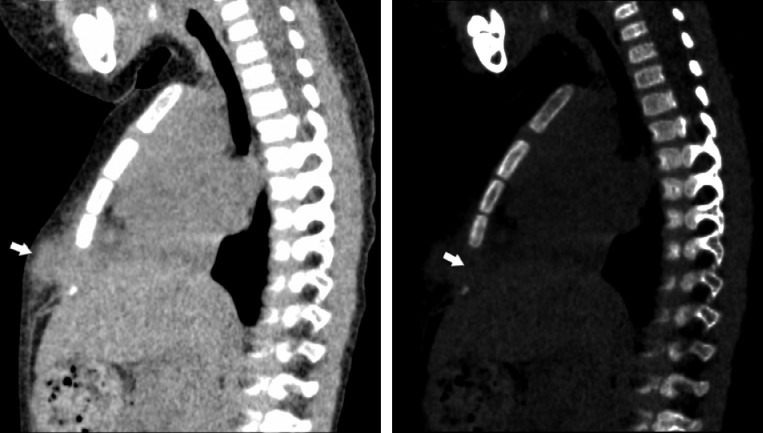

Fig. 1.

Nonenhanced sagittal computed tomography (A: mediastinal window, B: bone window) shows a dumbbell-shaped mass with a widening of the synchondrosis between the third and fourth elements of the sternal body. Sternal bone close to the tumor is not affected.

A previously healthy 2-year-old boy with a chief complaint of a rapidly growing sternal mass was referred to the Department of Pediatrics at our hospital. Physical examination revealed a 2-cm solid presternal mass lesion with localized pain. He had no fever or focal skin color changes. Laboratory examination of the patient's blood showed mildly elevated C-reactive protein (3.5 mg/dL) and white blood cell count (10,100/mm3). Computed tomography (CT) images revealed a dumbbell-shaped mass between the third and fourth elements of the sternal body with widening of the synchondrosis (Fig. 1A). The sternal bone close to the tumor was not affected (Fig. 1B). We suspected a SELSTOC based on the patient's characteristic imaging findings, and a wait-and-see approach was applied. The mass decreased significantly 3 days later, and completely disappeared 2 weeks later, as confirmed by palpation. The final diagnosis of SELSTOC was made based on characteristic image findings and the patient's clinical course.